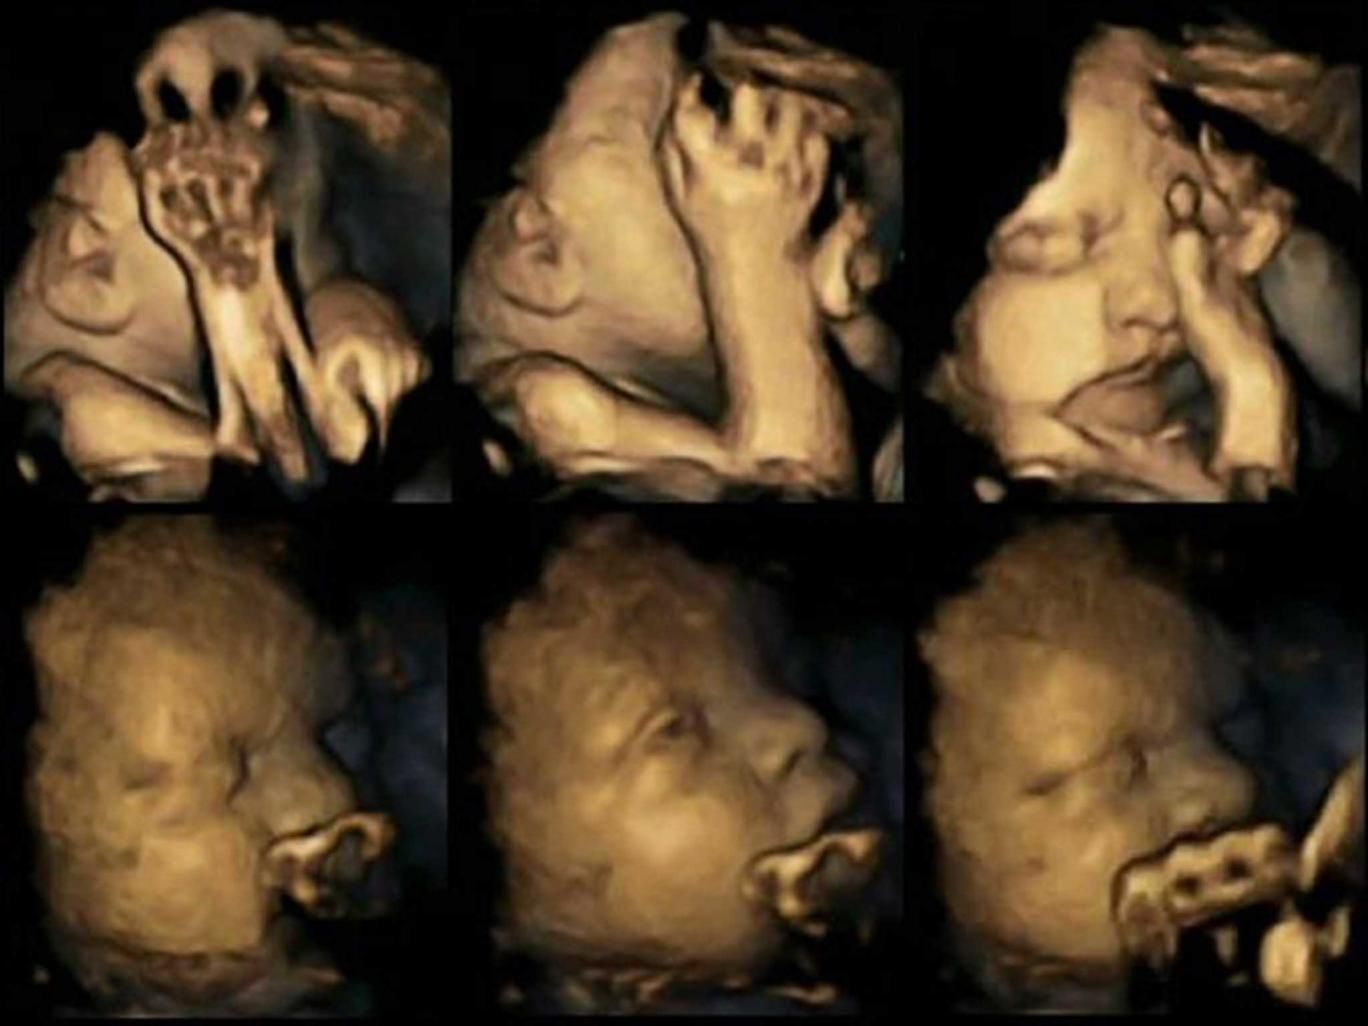

/ 5USG 4D

USG 4D - efekt palenia papierosów przez matki w ciąży

USG 4D - efekt palenia papierosów przez matki w ciąży © independent.co.uk

Amerykańska agencja zwalczania i zapobiegania chorobom postanowiła wykonać badanie, w którym udział wzięło 20 kobiet w ciąży. Kilka z nich paliło papierosy, średnio 14 dziennie.

Badanie polegało na wykonywaniu USG w 24, 28, 32 i 36 tygodniu ciąży. Nie było to zwykłe USG, a USG 4D, które pozwala nagrać film z wnętrza macicy w trójwymiarze. Taki obraz pozwala na dokładniejszą obserwację dziecka, oglądanie ruchów dziecka i grymasów na twarzy.

Na zdjęciu powyżej widać obraz z USG matki palącej papierosy, zaś poniżej nieplącej.

Takie nagrania wykonane, dzięki USG 4D były analizowane przez naukowców pod dwoma kategoriami ruchów płodów. Dokładniej dotyczyły one: dotykania twarzy i otwierania ust. Ilość takich ruchów wzrasta wraz z rozwojem ciąży.

A dokładniej rozwojem ośrodkowego układu nerwowego, dzięki któremu dziecko może odpowiednio kontrolować swoje ruchy. Często występują też zaburzenia układu sercowo-naczyniowego i przemiany materii. Różnice w rozwoju dzieci matek palących i niepalących są bardzo duże.